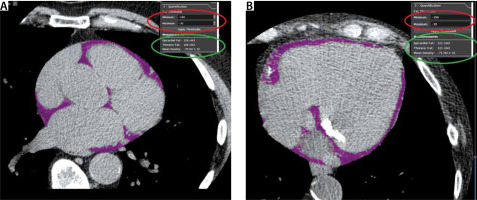

FIGURE 3

Example of cardiac CT acquired EAT volume from non-contrast enhanced images used to determine the Agatston calcium score. Panel a shows an upper axial slice of the heart. Panel B shows an axial slice at the level of the mitral valve. Note the mitral annular calcification. After manual contouring of the pericardium in the axial slice, the software calculates the voxels within the region of interest (ROI) with a CT attenuation coefficient attributed to adipose tissue. In this case, the filter setting defines adipose tissue as the voxels with CT attenuation number ranging from –190 HU to –30 HU (marked in the red ellipse). By summing all axial slices portraying the pericardium, the total EAT volume is calculated and mean EAT radiodensity expressed in HU is calculated (marked in the green ellipse)